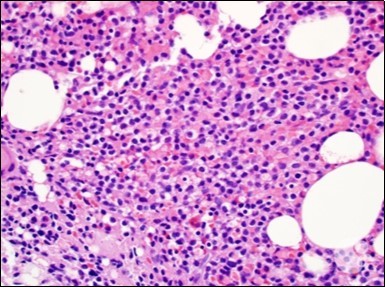

Figure 3.HCL: hairy cells dispersed within the native architecture(19).

The leukaemia cells may enunciate a characteristic immune phenotype, crucial for a confirmatory diagnosis. The peripheral blood mononuclear B cell population may display a kappa or lambda light chain restriction. The phenotype of classic hairy cell leukaemia may be delineated by concurrent, immune reactive CD19+ CD20+,CD 11c+, CD25+, CD103+ and CD123+. An intensely immune reactive CD200+ and a non reactive CD27- antigen may be present2, 4. Evaluation of a trephine bone marrow biopsy and bone marrow aspirate may define the degree of tumour infiltration. A dry tap on account of prominent bone marrow fibrosis may be elucidated at preliminary diagnosis. A decline in the normal haematopoiesis may account for a hypo-cellular marrow in 10% instances. Gradation of cellular infiltrating of the leukaemia within the bone marrow may be appropriately investigated with immune –histochemical stains2, 4. Immune staining for CD20+, annexin 1 and VE1 (a BRAF V600E stain] may validate the diagnosis and precisely analyse the extent of malignant bone marrow infiltration[8]. Determination of BRAF V600E mutation may be critical in therapeutically non responsive individuals with applicable standard therapy or in instances of multitudinous reoccurrences[9]. Deploying inhibitors of BRAF V600E gene may be efficacious in patients impervious to approved therapy. The mutation necessitates a comprehensive scrutiny of the implicated individuals with a sensitive molecular assay which may discern up to < 10% of the hairy leukaemia cells appearing in the peripheral blood smears or bone marrow aspirates diluted with peripheral blood or aspirates elucidating a dry tap[2,4]. Allele specific polymerase chain reaction (PCR) or a next generation sequencing may be optimally employed to circumvent false negative outcomes. If the leukaemia cells are sparse or if particularly sensitive & efficacious molecular techniques are not accessible, the application of appropriate immune histochemical stains to the bone marrow biopsy such as a BRAF V600E mutation stain (VE1) may detect the hairy cells and conclusively diagnose the condition[2,4,10]. Figure 1, Figure 2, Figure 3, Figure 4, Figure 5, Figure 6, Figure 7, Figure 8, Figure 9, Figure 10, Figure 11, Figure 12, Figure 13, Figure 14.